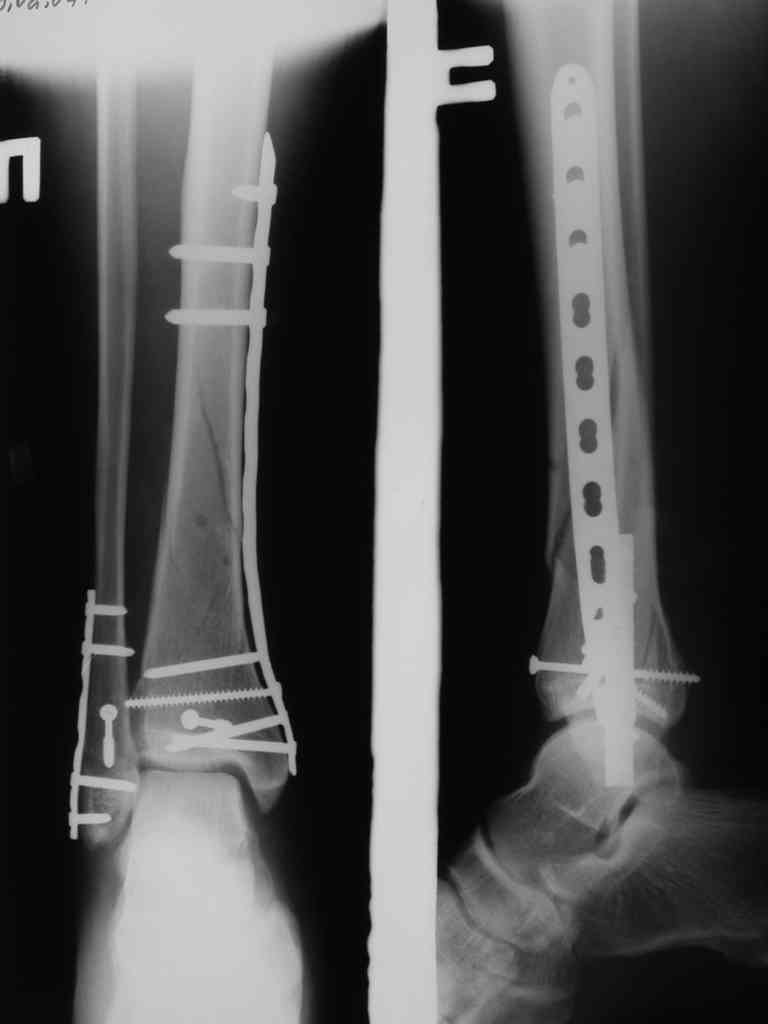

Сегодня прооперировали. Длительность 4-50. Начали как и говорил сверху вниз линейным разрезом - фиксация задне-латерального отломка к проксимальному 2мя винтами, затем "прилепили" к ним передне-медиальный (пришлось повозиться - была интерпозиция и довольно "сложный" винт) - к проксимальному 1 винтом и к задне-латеральному 1 винтом.Кстати на фото видно - у передне-медиального отломка еще осколок в области сустава, несколько смят. Далее началось веселье - второй доступ - задне-наружный к латеральной лодыжке и заднему краю, но оказалось, что задний край больше задне-медиальный (по снимкам было непонятно). Плюс к этому репозиция его мягко говоря сложновата (больной на спине, стол низкий и не поднимается). В общем выставили, фискировали 2мя винтами, на ЭОПе вроде стал, только верх отошел. Латеральную лодыжку заведующий решил интрамедуллярно (не хотел еще винты толкать), сначала 3мм спицей - нестабильно, затем 4мм стержень (не помню по автору) - ОК (кстати в месте перелома мелкая крошка - дефект до 5х7 мм по кортикалу). Ну медиальная лодыжка стандартно - третий разрез - винт 3,5 мм. Визуально все стабильно. На Р-контроле - видна небольшая ступенька заднего края по одному из контуров.

Рентгенограммы

Нельзя ли попросить снимки именно голеностопного сустава. Представлены снимки голени в нижней трети.Сустав фактичеси не виден.

Александр, если вы имеете в виду послеоперационные Р-граммы - то это все что есть. А сустав виден достаточно, чтобы оценить то что есть

Есть подозрение, что имеется ступенька заднего края, внутренняя лодыжка оттопырена. Взаимоотношения в суставе важнее, чем точная репзиция диафиза.

В боковой проекции - диастаз, 0,5-1мм.